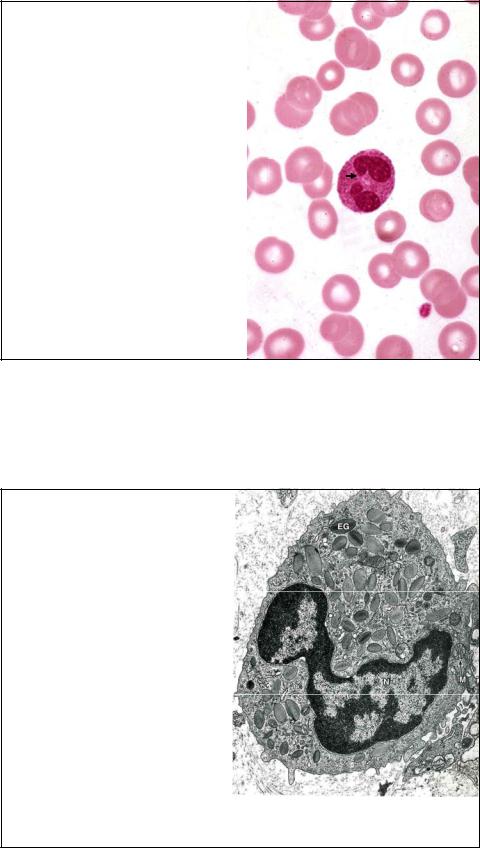

Эозинофил в мазке крови. x 1325.

Эозинофилы имеют |

|

|

диаметр 10-14 мкм и |

|

|

содержат многочисленные |

RBC |

|

крупные |

красно- |

|

оранжевые, |

|

|

светопреломляющие |

|

|

специфические гранулы. |

|

|

Присутствуют |

и |

|

азурофильные |

гранулы. |

|

Ядро коричнево-черное, |

|

|

двудолевое, |

напоминает |

|

сардельки, соединенные |

Pl |

|

тонкой |

перетяжкой |

|

(стрелка).